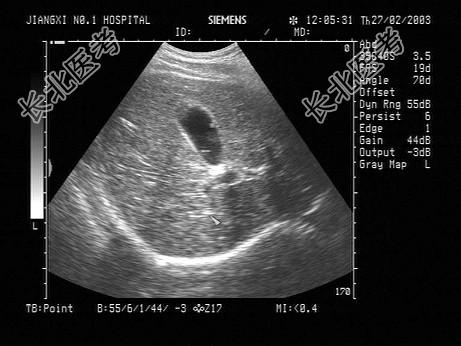

- 单项选择题男性患者,37岁, 健康体检,偶感上腹不适。声像图如图所示, 诊断为 ( )

A、胆囊癌

B、胆囊息肉

C、胆汁淤积

D、胆囊腺瘤

E、胆囊结石